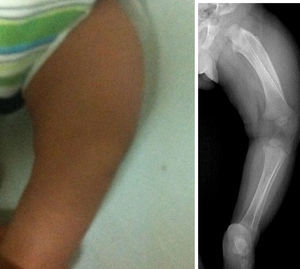

Los estudios de imágenes solicitados fueron radiografías simples de diferentes segmentos corporales, que demostraron una reacción perióstica (periostitis e hiperostosis) con cambios escleróticos, sin lesiones osteolíticas. Se apreció compromiso de la rama mandibular, el fémur izquierdo, la tibia y el radio bilateral. No se observaron microfracturas ni lesiones que involucraren metáfisis (figs. 1–4).

Pierna izquierda.

Estudio radiográfico de pierna izquierda. Proyección AP que demuestra afección severa en el fémur izquierdo. Nótese hiperostosis discreta en la cara anterior de la tibia izquierda y el engrosamiento cortical del radio. Los núcleos de osificación y las epífisis no presentan cambios.